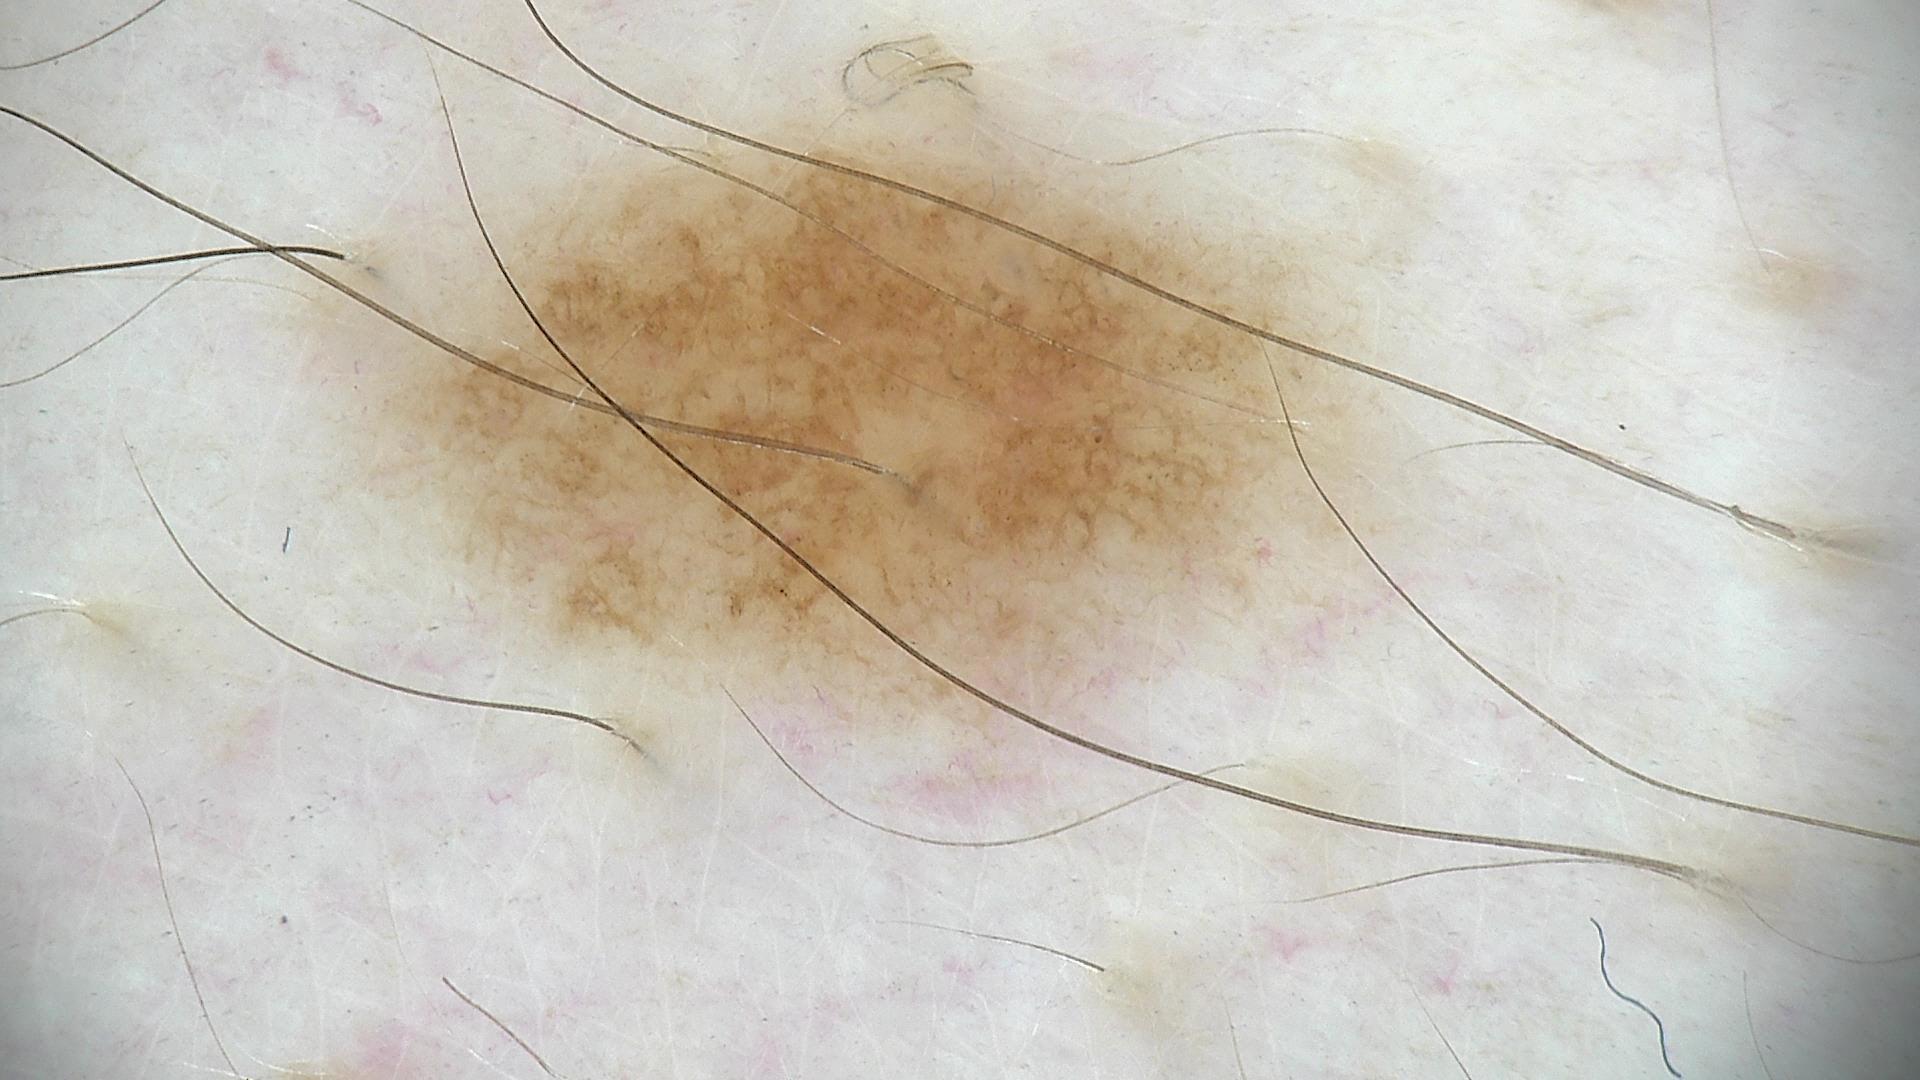

ISIC_4389890

diagnosis_1

Benign

diagnosis_2

Benign melanocytic proliferations

diagnosis_3

Nevus

diagnosis_4

Nevus, NOS, Compound

image_type

dermoscopic

melanocytic

True

patient_id

IP_8658032